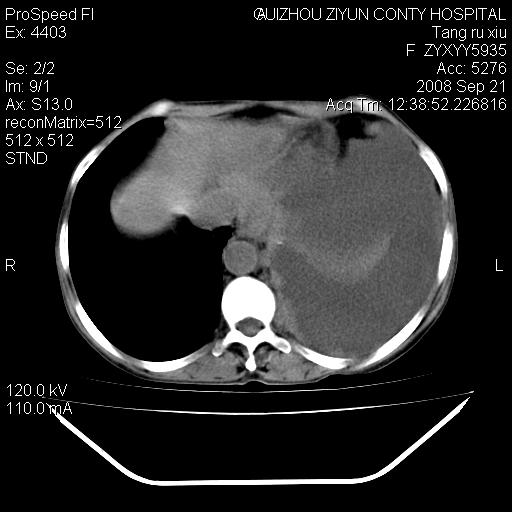

f、57岁,上腹痛.2月,近来胸闷。2月前在外院摄胸片示左侧胸腔少量积液。

(患者腹痛入院,欲吐,临床医生说禁饮,所以没有口服对比剂)

考虑----左侧胸腹腔积液----压迫性肺不张----心包积液---肝脏多发低密度影-----穿刺抽液后复查

左侧胸壁见一结节影,肝脏多发低密度影,左侧胸腔大量积液。建议增强

1)考虑左侧肺癌侵犯纵隔,左侧胸膜、肝脏及腹膜后淋巴结转移。2)左侧胸腔积液。3)心包积液。

肝脏大小形态尚可,其实质内可见多发大小不等的低密度影,边缘模糊。肝门区结构紊乱,腔静脉腹主动脉旁可见多发软组织密度影,部分融合成团块状,并向下延伸。胰腺及十二指肠结构显示不清。腹腔内脐后肠管走形僵硬,管壁可见增厚。盆腔内可见多个淋巴结影。所扫层面左侧胸腔可见大量弧形水样密度影,其内侧可见被压缩的肺组织影。左侧胸壁可见一小结节样软组织密度影,边缘模糊。心脏纵隔向右侧移位。心脏包膜内可见囊样低密度影,其内侧心房室周围可见一圈气体样密度影。纵隔内大血管旁可见多发软组织团块影,部分融合。

1.腹膜后淋巴瘤侵及肝脏,肺内及纵隔内多发转移。2.左侧大量胸腔积液并压缩性肺不张。3.心包脓肿可能,转移不除外。4.脐后局部肠管管壁增厚,考虑炎症可能,肿瘤不除外。